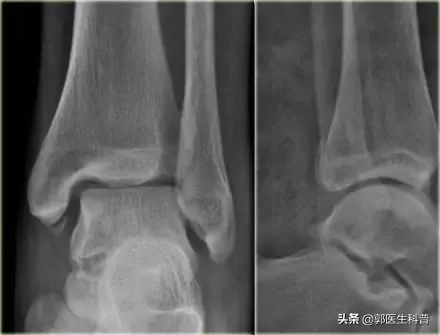

受伤后,首先看看受伤部位肿胀程度,以及疼痛程度,一般来说如果肿胀疼痛不是很重,可以自己尝试轻微活动脚踝部,但不要负重,脚踝疼痛不剧烈,大多是扭伤;但不要勉强走路,以免加重损伤,如果自己活动足踝时感觉剧烈疼痛,局部肿胀明显、皮下瘀血明显、不能站立和走动,疼的地方在骨头上,应立即去医院让医生面诊触摸检查,必要时行X线片、CT或者核磁共振检查,排除骨折韧带损伤,以免留下后遗症。